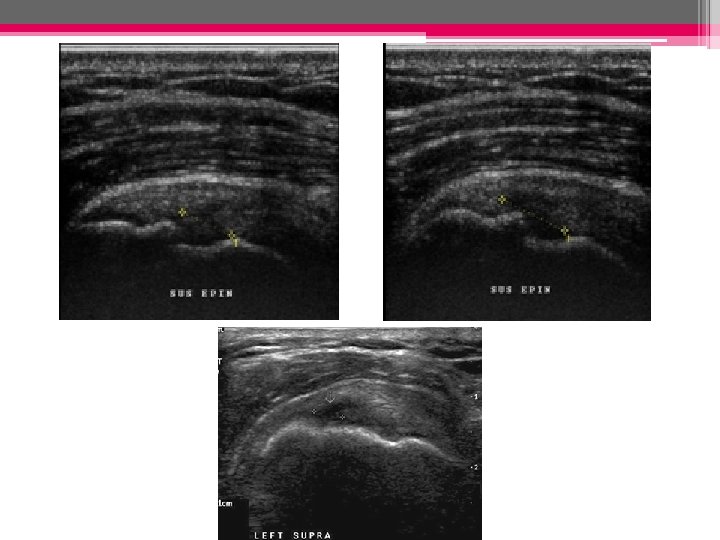

ECHOGRAPHIE: • Rupture transfixiante signes directs: - Méplat tendineux ou marche d’escalier - Défect tendineux focal (hypo ou anéchogène (hyper très rare) - Amincissement du tendon - Disparition du tendon

Rupture transfixiante Défect tendineux focal anéchogène du sus-épineux Amincissement du tendon sus-épineux Absence d’individualisation du tendon ; le muscle deltoide vient directement au contact de la tete humérale

• Rupture complète: Rupture totale: important amincissement et perte de la convexité supérieure du tendon Rupture totale: désinsertion des fibres distales remplacées par du liquide )

Supraspinatus tendon, longitudinal view. Massive supraspinatus tendon tear with tendon nonvisualization and joint fluid collection. The stump of the supraspinatus tendon (arrows) is retracted.